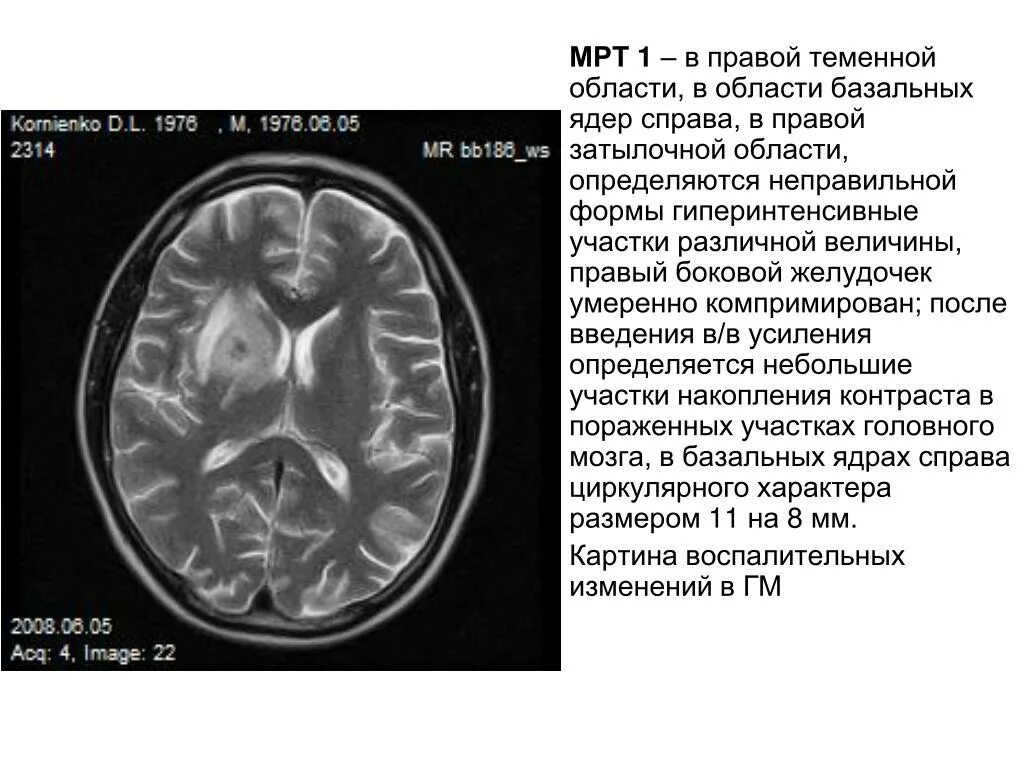

Киста базальных ядер слева